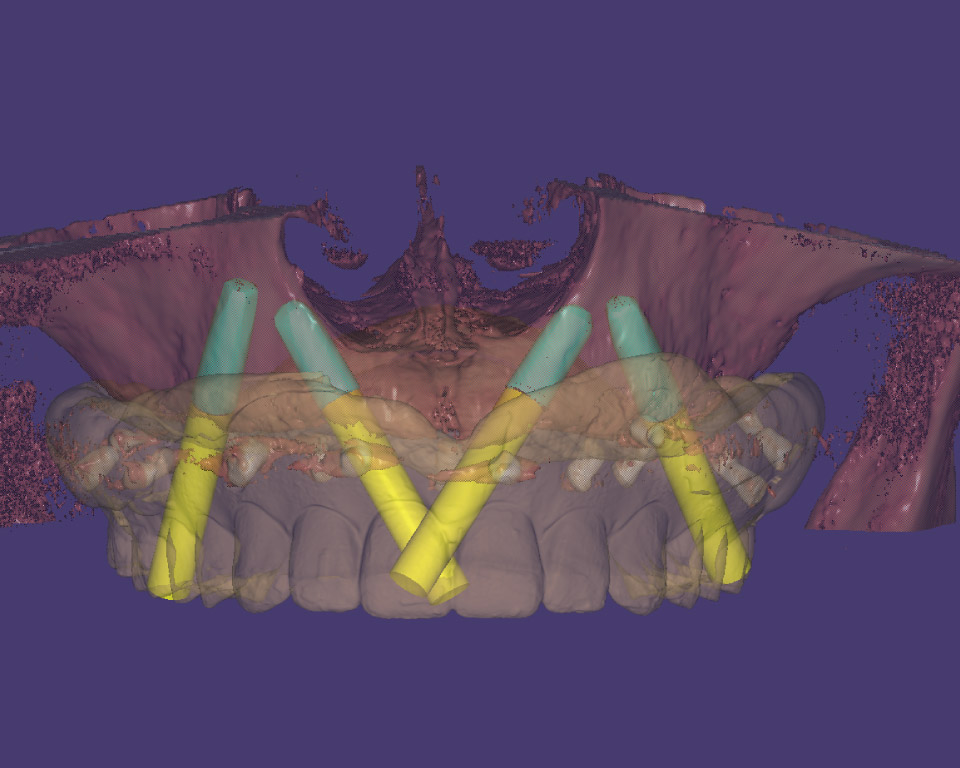

About Precision Dental Studio

Founded by MD & Master Technician Mr. Rahul Kakodkar & Director Mrs. Radhika Kakodkar in the year 1997, Precision Dental Studio Ltd. Opened its doors for business; guided by one principle - in search of Complete & Perfect Smiles.

Precision Dental Studio Ltd is a State of the Art High end Dental Laboratory situated in Thane West, Mumbai Maharashtra.